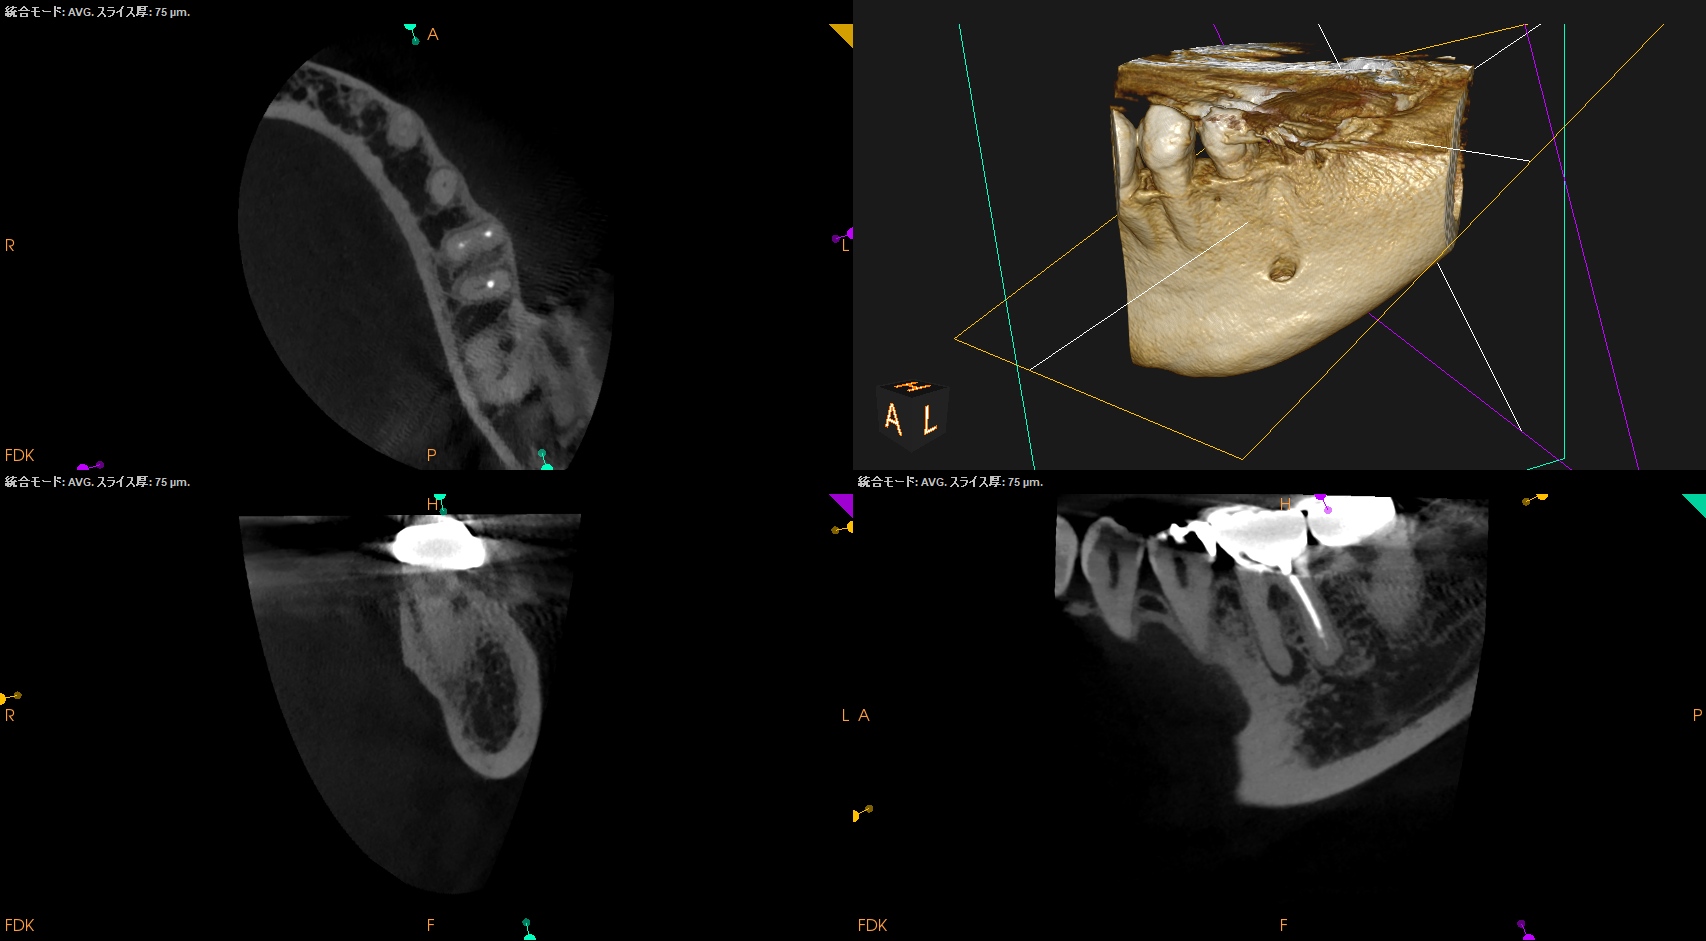

ということで臨在歯の#18もCBCTを精査した。

#18

M

D

#18 Mのこの絵は縁下カリエスの可能性を示唆している。

明らかにCBCTの存在がなければこの存在に気づけなかっただろう。

このことからも、

もはやCBCTの存在は歯内療法においてはマストである

ということがわかる。